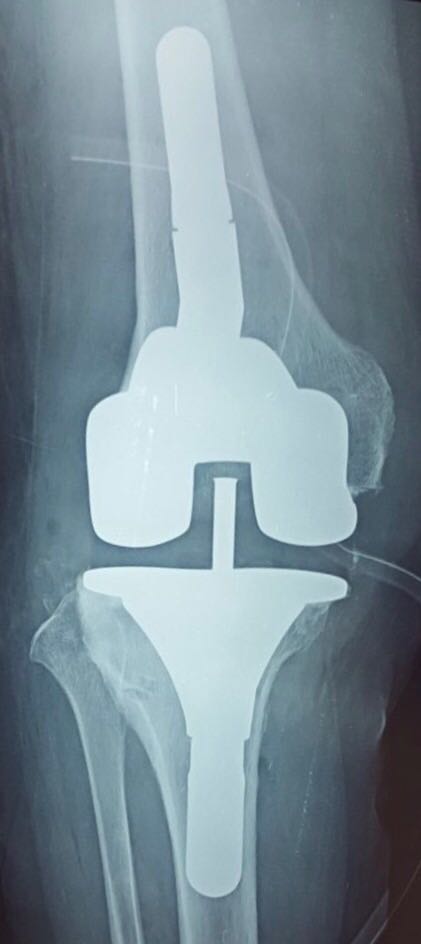

Gonarthrose sur Genu Valgum